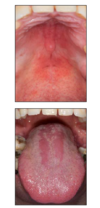

What is this infectious disease?

Describe it

HSV‐1: Primary

Infection

it is a raised blister/papule on the

vermilion

The bottom arrow pointing to a mucosal

ulcer w/ tan pseudomembrane.

What is this infectious disease?

Describe it

HSV 1- Primary Herpetic

Gingivostomatitis

Ulcer with an erythematous halo (top two arrows). We

also have ulcerations that are irregular in shape on the gingiva

(bottom two arrows).

These photos represent

gingivostomatitis

multiple irregularly shaped

ulcers present on the fixed and movable mucosa, bilaterally

What is this infectious disease?

What probably this patient also have?

HSV1: primary herpetic gingivostomatitis

there are multiple irregularly shaped

ulcers present on the fixed and movable mucosa –> most likely

diagnosis is primary herpetic gingivostomatitis since the patient has

fever and malaise.